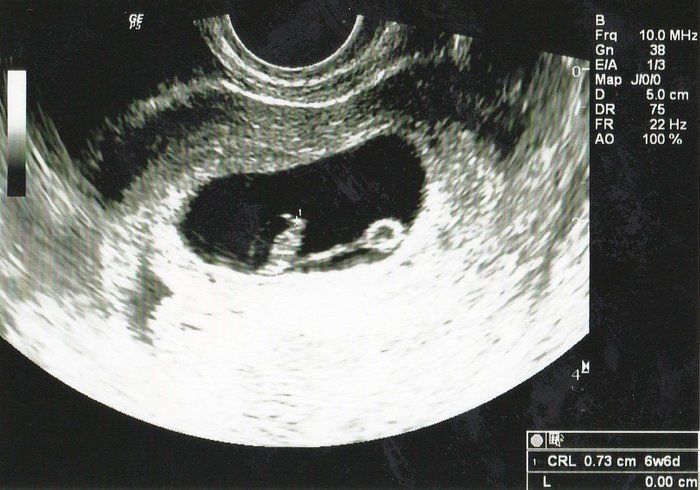

小吉さんの妊娠6週目のエコー写真

待ちに待った診察の日です。自分の中では妊娠していると確信がありましたが、医師のお墨付きをもらわなければなりません。先週よりも大きくなった胎嚢の中に赤ちゃんの姿が見えます。このときは0.7cmですが、心音が確認できたことが決め手となり妊娠が確定しました。しかし、妊娠初期での流産リスクは25%と告げられ、落ち込む暇もなくどのようにして乗り切るかを考え始めました。